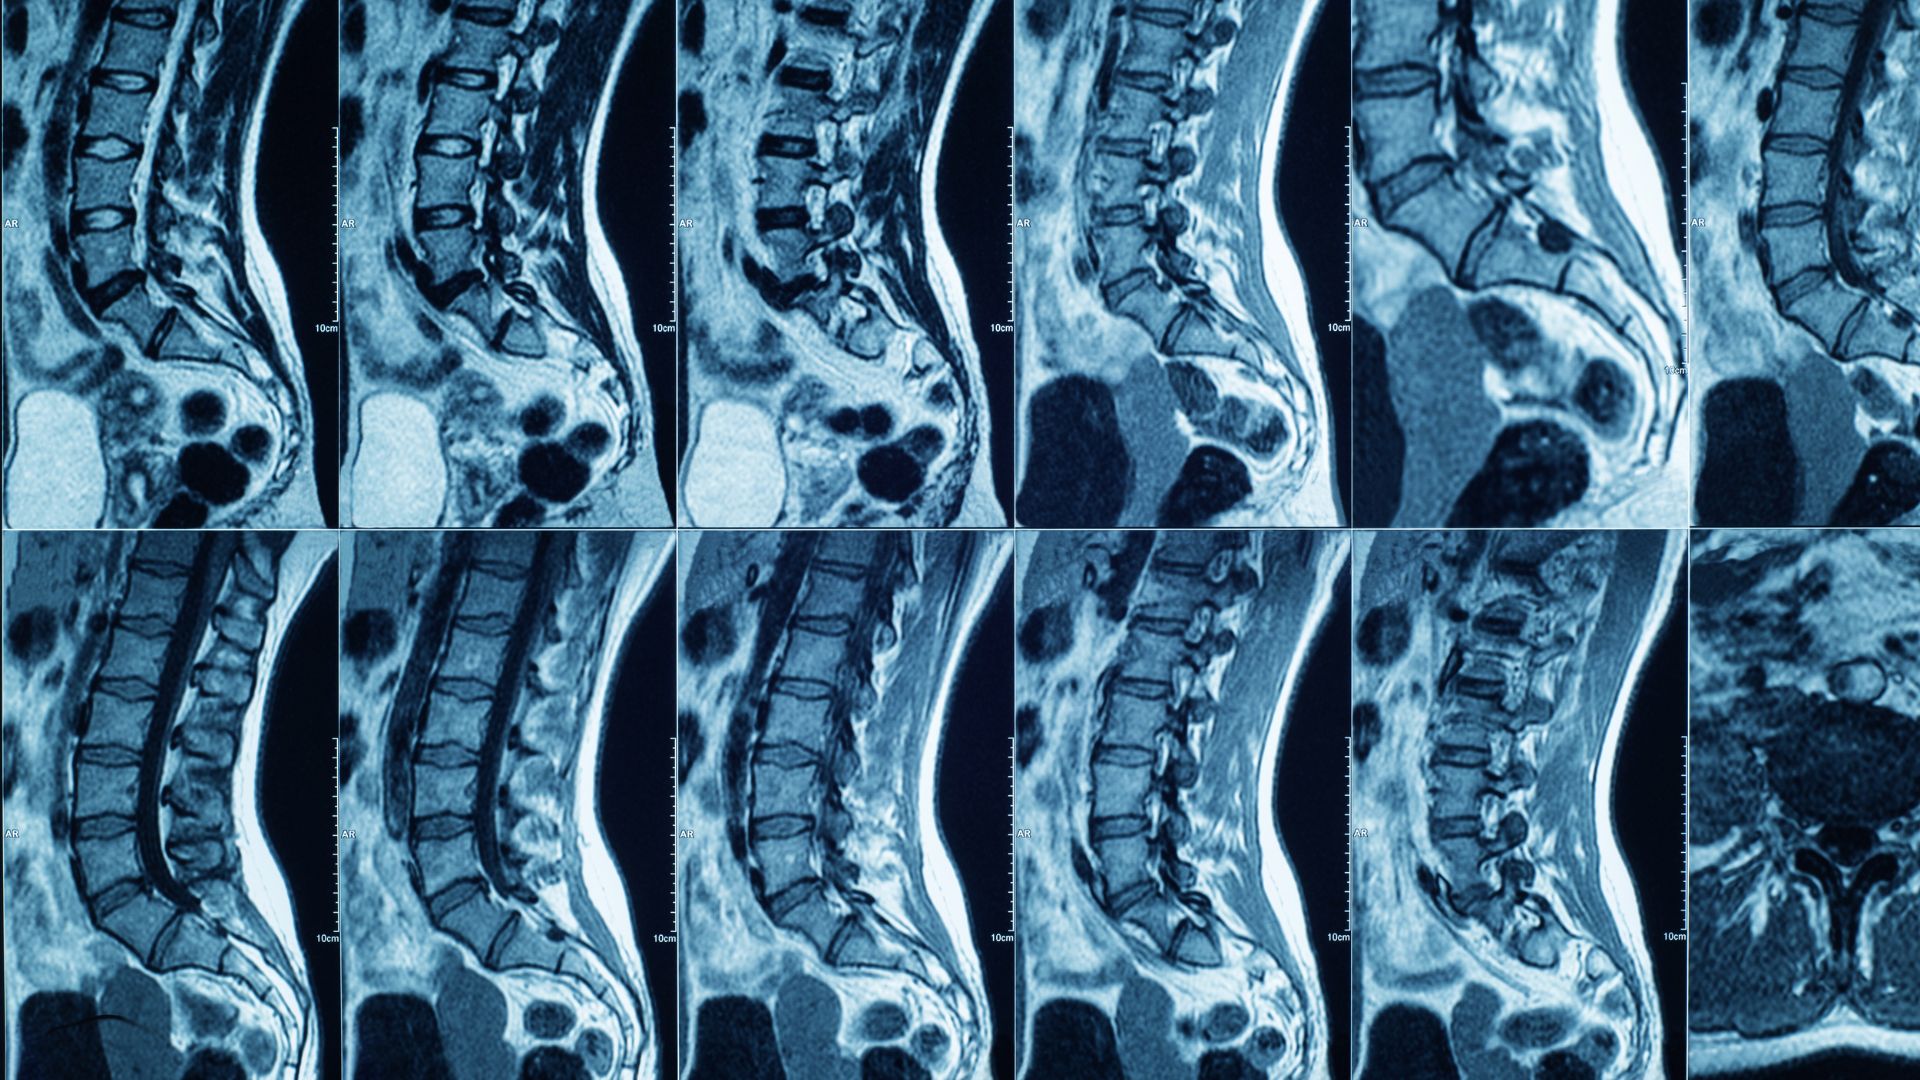

Chụp MRI cột sống phát hiện thoát vị đĩa đệm là kỹ thuật sử dụng cộng hưởng từ để tạo ra hình ảnh chi tiết của cột sống, trong đó thể hiện rõ đĩa đệm, tủy sống và các rễ thần kinh xung quanh. Phương pháp này cho phép bác sĩ xác định chính xác vị trí đĩa đệm bị thoát ra khỏi vị trí bình thường, mức độ chèn ép thần kinh và các tổn thương đi kèm nếu có.

Thoát vị đĩa đệm xảy ra khi phần nhân nhầy bên trong đĩa đệm thoát ra ngoài, chèn ép vào rễ thần kinh hoặc tủy sống, gây đau và rối loạn vận động. Những tổn thương này thuộc nhóm mô mềm, rất khó quan sát bằng X-quang thông thường. MRI có ưu thế vượt trội trong việc tái tạo hình ảnh mô mềm, giúp bác sĩ nhìn thấy rõ cả những thay đổi nhỏ mà các phương pháp khác dễ bỏ sót.

Một trong những giá trị lớn nhất của MRI là khả năng đánh giá chi tiết mức độ thoát vị đĩa đệm. Hình ảnh cộng hưởng từ cho phép phân biệt rõ các dạng thoát vị khác nhau, từ lồi đĩa đệm nhẹ đến thoát vị nặng có chèn ép mạnh vào thần kinh.

Dựa trên kết quả MRI, bác sĩ có thể xác định đĩa đệm thoát vị ở tầng nào của cột sống, mức độ ảnh hưởng đến tủy sống hoặc rễ thần kinh ra sao. Điều này có ý nghĩa rất lớn trong việc lựa chọn phương pháp điều trị. Với những trường hợp thoát vị nhẹ hoặc trung bình, điều trị nội khoa kết hợp phục hồi chức năng thường mang lại hiệu quả tốt. Ngược lại, những trường hợp chèn ép nặng, có nguy cơ tổn thương thần kinh kéo dài có thể cần can thiệp chuyên sâu hơn.